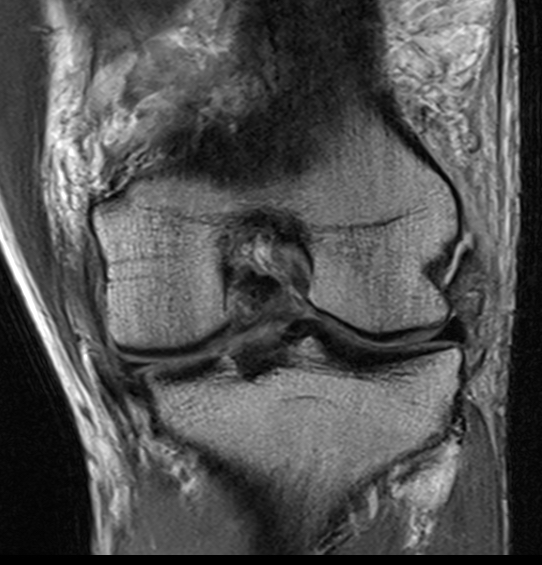

LCL

Harder to see on a single image. Need to scroll through coronal images

Coronal MRI with normal femoral insertion of LCL and popliteus